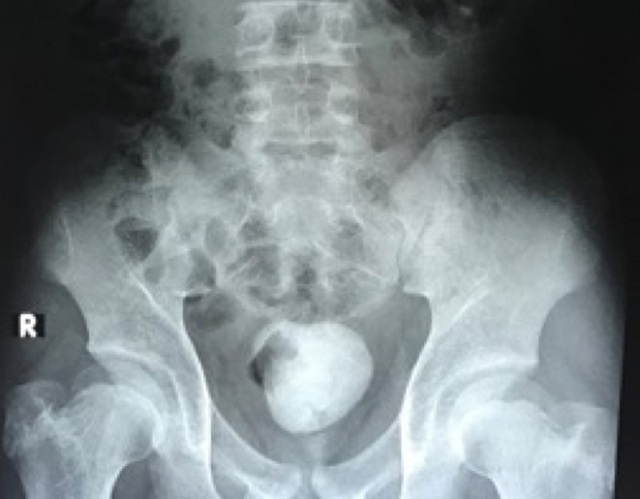

Hình ảnh X-quang cho thấy viêm sỏi bệnh nhân to nằm ở bàng quang.

Tương tự ở lần này, các xét nghiệm và kết quả khảo sát hình ảnh cho thấy bệnh nhi bị sỏi bàng quang tái phát với kích thước lớn khoảng 10cm.